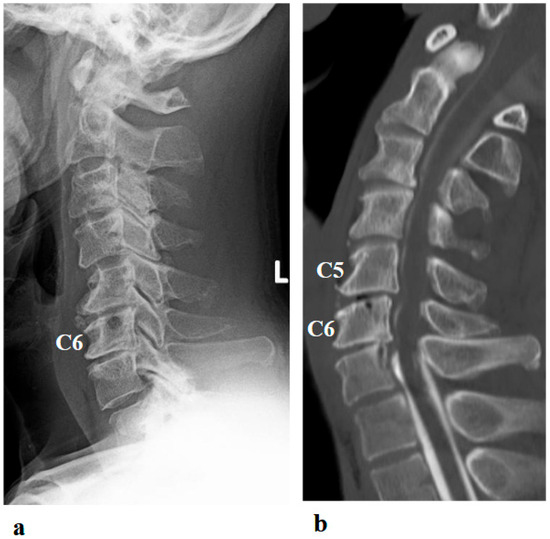

Hybrid Assistive Limb Treatment for the Shoulder and Elbow Joints Enabled Recovery from Chronic-Phase Severe C5 Palsy Following Cervical Spine Surgery

J. Clin. Med. 2025, 14(21), 7520; https://doi.org/10.3390/jcm14217520 - 23 Oct 2025

Postoperative C5 palsy is a common complication of cervical spine surgery. Inadequate recovery from C5 palsy can result in significant impairment of activities of daily living. However, no effective treatment has been established for persistent cases. In the present report, we describe a [...] Read more.

Postoperative C5 palsy is a common complication of cervical spine surgery. Inadequate recovery from C5 palsy can result in significant impairment of activities of daily living. However, no effective treatment has been established for persistent cases. In the present report, we describe a novel therapeutic approach using the Hybrid Assistive Limb (HAL) in a patient with severe, prolonged postoperative C5 palsy. The patient was a 46-year-old man who developed severe right C5 palsy following cervical spine surgery performed 41 months earlier. Despite undergoing conventional rehabilitation, no improvement was observed, and the muscle strength of the right deltoid and biceps remained at manual muscle testing (MMT) grade 2. HAL training, using both shoulder and elbow devices, was initiated at our institution. Training was conducted once weekly for a total of 106 sessions over 21 months. At baseline, the right shoulder range of motion was limited to 50° in flexion and 35° in abduction. With HAL-assisted training, flexion improved to 150° and abduction improved to 95° by the final (106th) session and further increased to 165° and 170°, respectively, at long-term follow-up. Deltoid strength, assessed using handheld dynamometry, increased from 3.5 Nm/kg at baseline to 28.5 Nm/kg after training. In this case, a long-term therapeutic program incorporating shoulder and elbow HAL training successfully improved severe and prolonged postoperative C5 palsy to a functionally useful level. This case highlights the potential effectiveness of HAL therapy for treatment-resistant postoperative C5 palsy. Full article